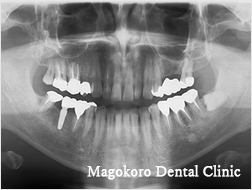

連続する複数の歯を失った場合

インプラントBr

インプラントを複数本埋入し、その上に連結した人口の歯を取り付けます。

必ずしも失った本数のインプラントが必要なわけではありません。かみ合わせを考慮し、必要な本数のインプラントを埋入します。